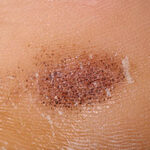

- Patients present with an irregular dark macule over the heel .

Examination reveals a blue-to-black macule or patch ranging in size from a few millimeters to several centimeters in diameter.

- On close inspection, multiple petechiae are centrally aggregated with a few scattered satellite macules.

- The dyschromia often is in a horizontal distribution; however, both circular and oval lesions may occur.